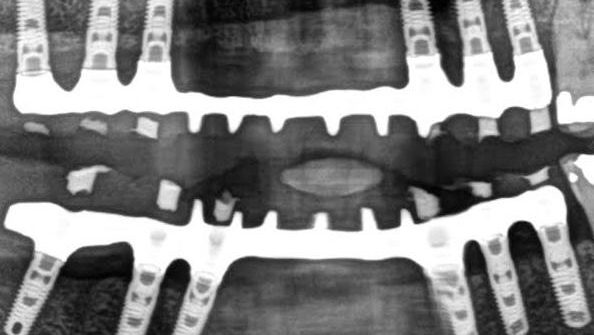

Los implantes de carga inmediata se presentan como la alternativa estética y funcional para aquellas personas que necesitan colocarse uno o más implantes en zonas visibles al hablar o sonreír, y no pueden o no desean esperar los meses necesarios para poder colocar una corona definitiva tras la integración del implante.